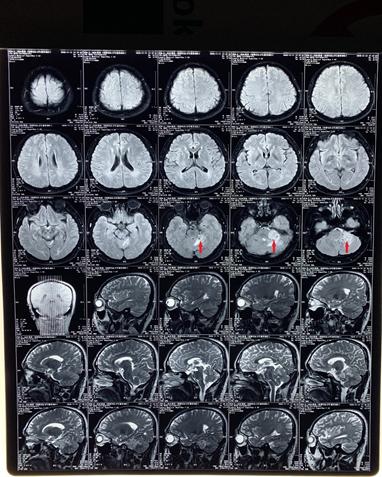

2、我院给予患者核磁共振检查(T1、T2)显示左侧桥小脑区占位性病变,结合临床考虑听神经瘤。

(MRI T1加权成像,红色指示病变区)

(MRI T2加权成像,红色指示病变区)